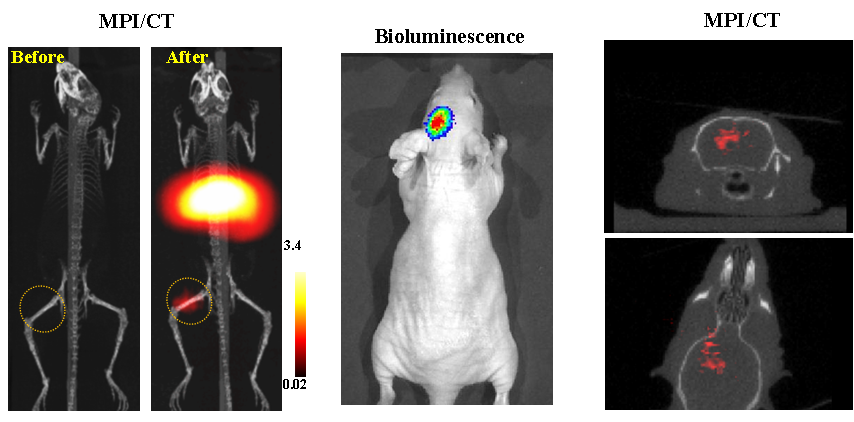

今年二月份,宋國勝教授與斯坦福大學(xué)饒江宏教授合作,通過系統(tǒng)的研究獲得了影響磁性粒子成像信號(hào)的作用規(guī)律和關(guān)鍵原理,開發(fā)了新型磁性粒子探針---FeCo合金粒子,并首次應(yīng)用于磁性粒子成像(MPI)。該造影劑在極低含量時(shí)(5 ng)仍具有很強(qiáng)的造影效果。這意味著,未來在進(jìn)行人體成像時(shí),可以使用更小劑量的造影劑,從而避免高劑量造影劑引起的腎肝損傷。基于MPI的直接成像原理,我們可以對造影劑進(jìn)行正相和無背景干擾的活體成像,極大地提高信噪比。這項(xiàng)技術(shù)為腫瘤早期診斷、癌細(xì)胞示蹤、腦中風(fēng)、藥物輸送治療、肺部灌注成像、胃腸出血、神經(jīng)退行性疾病、磁熱治療等在活體中的可視化研究,提供了強(qiáng)有力的手段。相關(guān)研究成果以湖南大學(xué)為第一單位發(fā)表在Nature 子刊《Nature Biomedical Engineering》(IF = 18.952)。該期刊是“生物醫(yī)學(xué)工程”的頂級期刊。宋國勝教授為該論文的共同通訊作者。